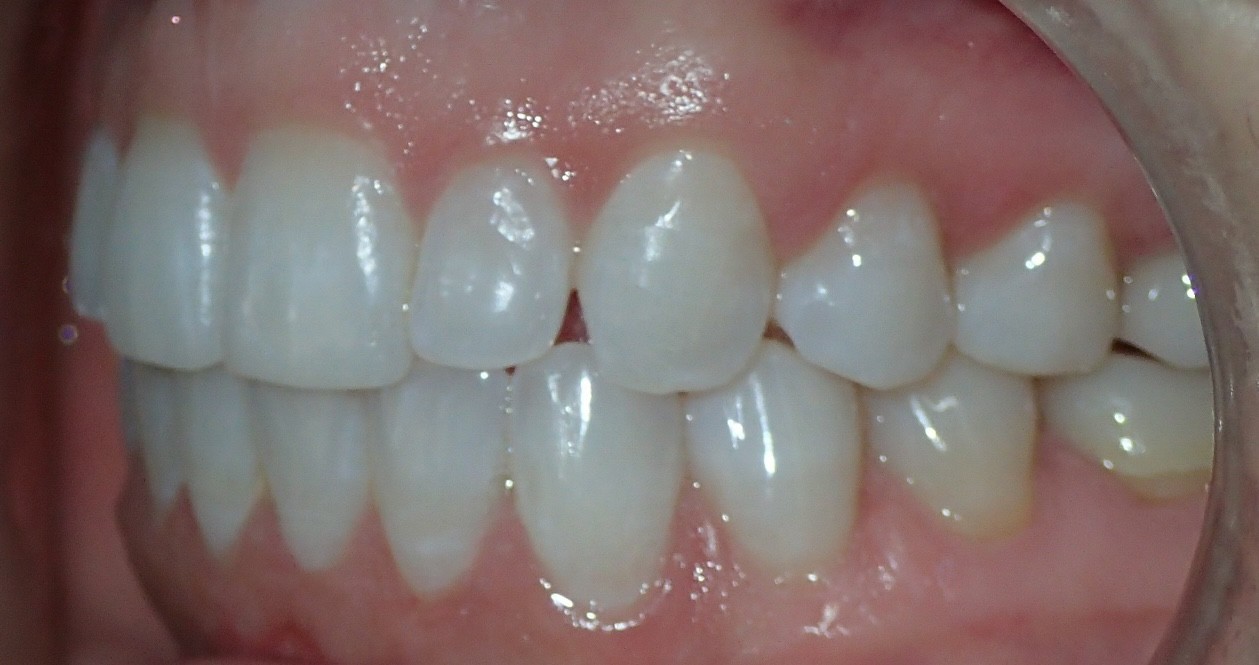

Final results

INTRAORAL